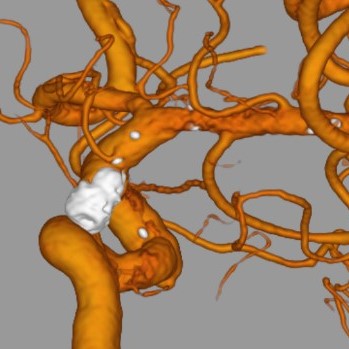

脳血管撮影

脳血管撮影では、頭頸部の血管をカテーテルから造影剤を流して撮影します。血管の走行を観察したり、必要に応じて血管の狭窄や閉塞を広げる治療や、動脈瘤をコイルで塞栓する治療、脳腫瘍などへの栄養血管に対して手術前の塞栓術を行ったりします。脳の血管をみる検査にはCTやMRIなどといった撮影もありますが、血管撮影装置での脳血管撮影ではそれらよりも細かい血管の状態まで観察することができます。

右内頚動脈瘤

右総頚動脈造影

術後3D